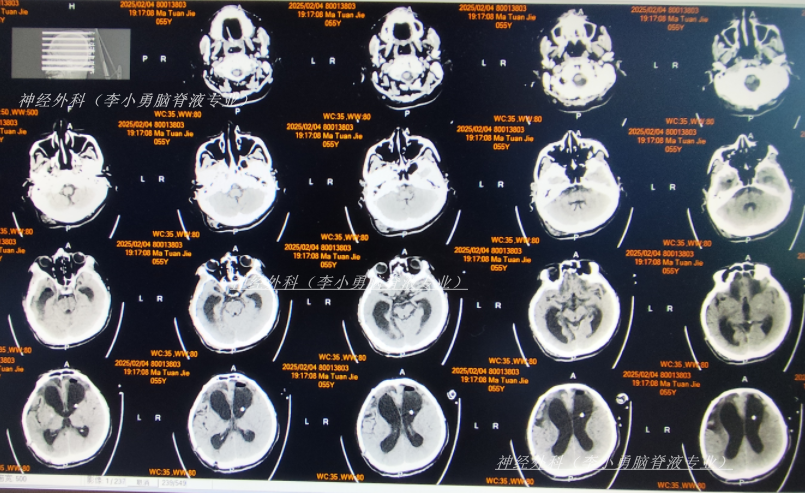

脑室腹腔分流术后13天即2024年10月2日,查头颅CT示去骨瓣术后,脑室分流术后状态,脑室仍有扩张(图-1);但意识有好转。

图-1:2024年10月2日头颅CT

脑室腹腔分流术后22天即2024年10月11日,查头颅CT示脑室缩小(图-2)。

图-2:2024年10月11日头颅CT

脑室腹腔分流术后28天即2024年10月17日,进行了颅骨修补术(图-3)。

图-3:2024年10月18日头颅CT

颅骨修补术后5天即2024年10月22日(脑室腹腔分流术后33天),查头颅CT示颅骨修补术后状态(图-4)。

图-4:2024年10月22日头颅CT